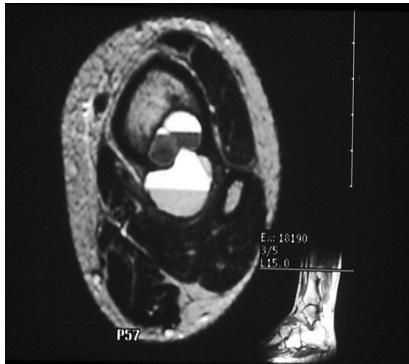

Aneurysmal Bone Cyst

site: Distal tibial

size:  Involving most of distal part

matrix: Cortical expansion, radiolucent matrix, well defined, narrow zone of transition

soft tissue involvement:  no peristeal reaction